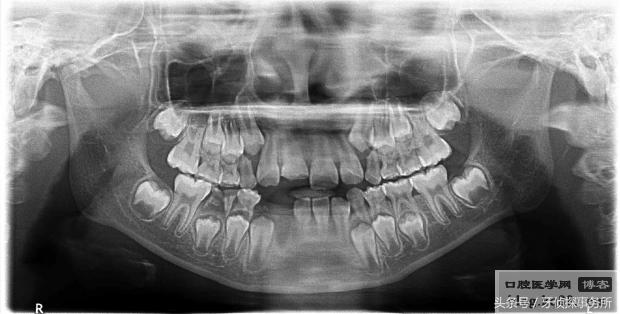

3、嵌入性脱位

嵌入,即牙齿陷入牙槽骨。如果伤及恒牙牙胚需要将嵌入的乳牙复位;如果是在替换牙期,可以将嵌入的乳牙拔除;其他情况可以不必处理,等乳牙自行长出。